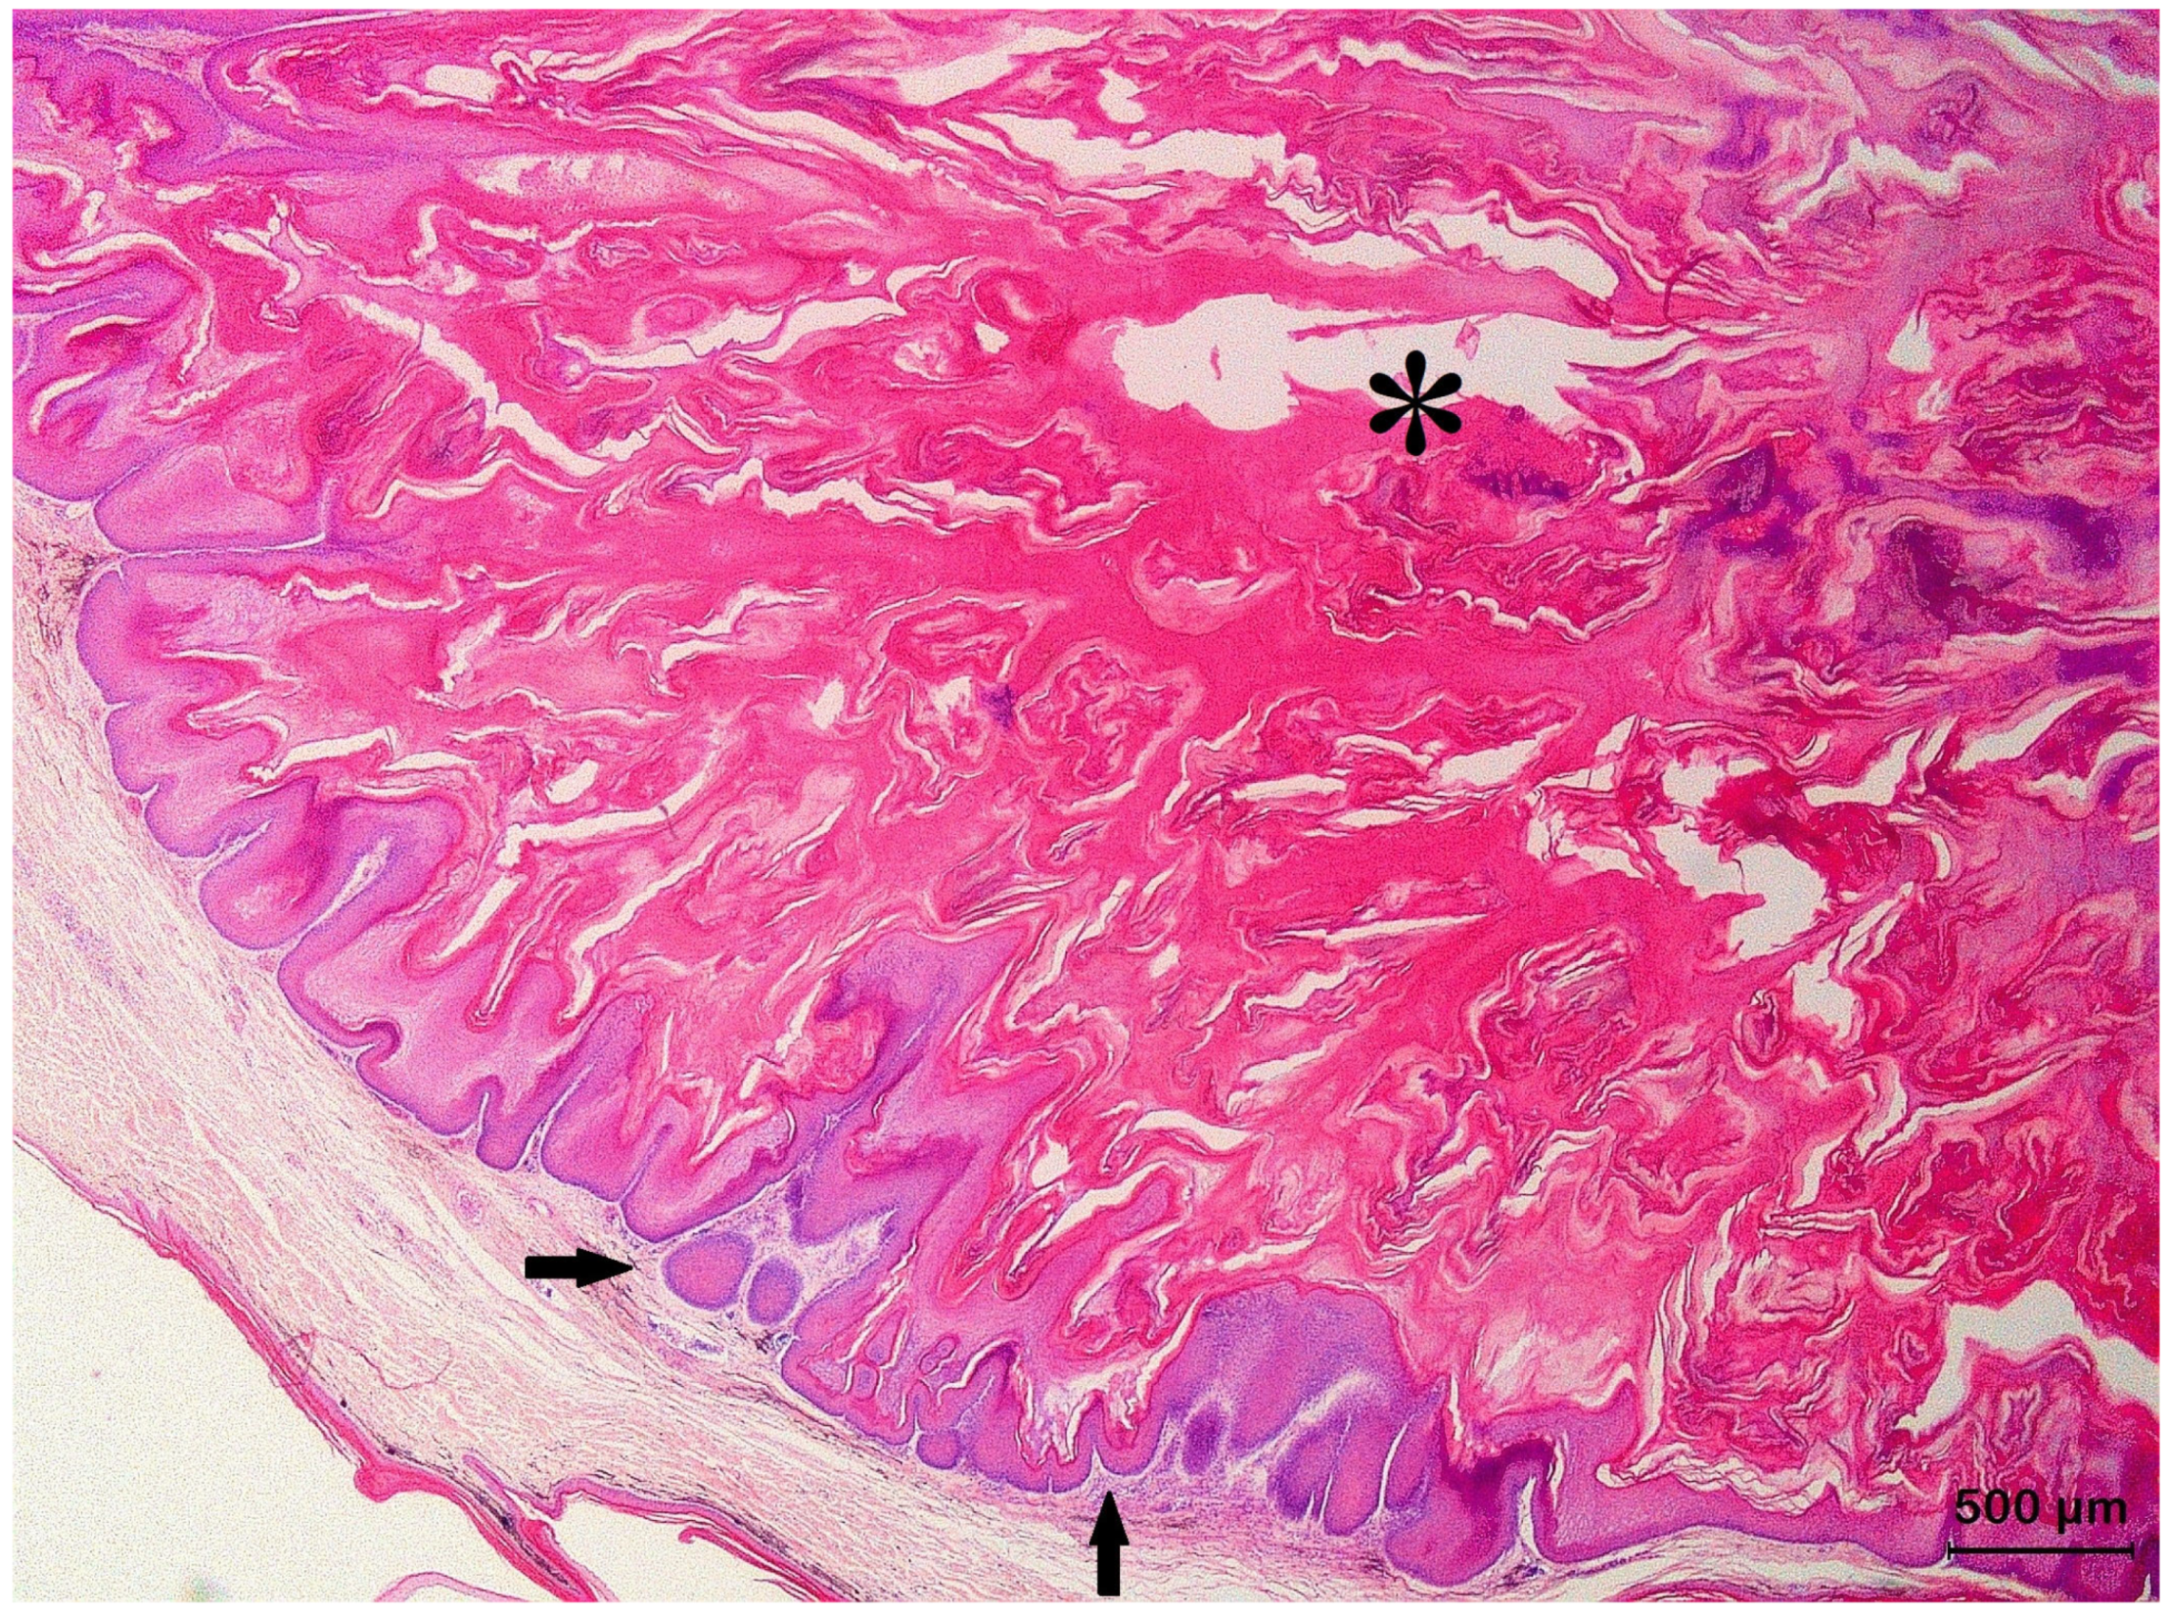

3.2. Squamous Cell Carcinoma and Its Histological Variants

3.3. Basal Cell Carcinoma and Its Histological Variants